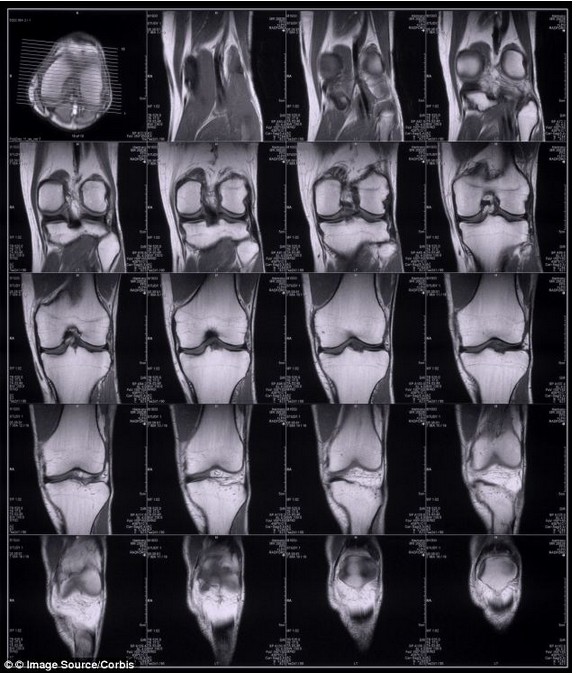

Как это будет работать? Исследователи надеются, что им удастся достаточно скоро создать портативный коленный сканер. Этот прибор должен успевать фотографировать коленную чашечку каждого человека, проходящего сквозь зону его действия. Компьютер к котором будут подключены такие приборы, будет сравнивать полученные снимки с информационной базой данных и почти мгновенно устанавливать личность.

Так новый прибор МРI сканер видит колени людей, проходящих сквозь контрольную зону аэропорта.